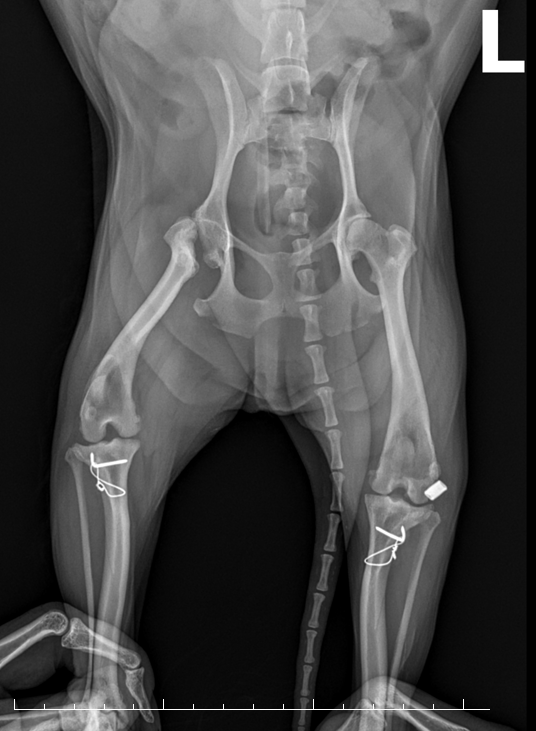

• X-ray 검사 이미지

02

X-ray 검사

무릎 관절을 체크하고,십자인대 단열을 확인합니다.

• 십자인대 수술 이미지

TPLO 십자인대 수술

절뚝거리는 증상으로 내원!

TPLO 수술 후 건강한 일상으로 복귀

• 슬개골 탈구 + 십자인대 이미지

MPL, TPLO 슬개골 탈구 + 십자인대

슬개골 탈구 수술과 십자인대 수술

동시 진행 케이스